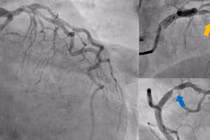

Kết quả chụp CT mạch vành 2560 lát cắt cho thấy ông bị tái hẹp gần như hoàn toàn ở trong lòng stent cũ và hẹp khít đoạn phía sau stent tại động mạch liên thất trước.

Các bác sĩ đánh giá đây là tổn thương tái hẹp mức độ nặng làm giảm khả năng cung cấp máu cho tim.

“Nhánh mạch máu chính nuôi tim đã hẹp gần hết, gây thiếu máu nuôi tim nghiêm trọng và có thể dẫn tới nhồi máu bất cứ lúc nào nếu không can thiệp kịp thời”, ThS.BS Nguyễn Đình Công, Phó khoa Tim mạch - Tim mạch can thiệp BVĐK Hồng Ngọc - Phúc Trường Minh, người trực tiếp thăm khám cho ông N. chia sẻ.

Trong quá trình can thiệp, ê-kíp đã sử dụng kỹ thuật siêu âm trong lòng mạch (IVUS) để quan sát trực tiếp cấu trúc mạch vành và stent.

“Kết quả cho thấy stent cũ có kích thước nhỏ hơn đường kính thực tế của mạch máu, khiến stent không thể mở rộng hết lòng mạch, đồng thời mảng xơ vữa đã phát triển mạnh mẽ cả bên trong lẫn phía ngoài stent. Đây là nguyên nhân gây tái hẹp nặng cho người bệnh”, bác sĩ Hải chia sẻ

Tuy nhiên, ca can thiệp đối mặt với một khó khăn lớn khi trong quá trình nong bóng để mở rộng đoạn mạch máu bị hẹp thì vị trí tổn thương ở phía ngoài stent bị tách ra khỏi thành mạch (bóc tách động mạch).

Các bác sĩ nhận định với tính chất tổn thương mạch vành trong trường hợp này thì phương án nong bóng phủ thuốc không còn phù hợp. Ê-kíp lập tức chuyển sang chiến lược đặt stent mới.

Nhờ tính toán các phương án can thiệp kỹ càng và thay đổi kế hoạch can thiệp nhạy bén, người bệnh nhanh chóng được đặt 01 stent có kích thước dài giúp bao phủ toàn bộ vùng tổn thương phía trong và sau stent cũ.

Kết quả IVUS sau can thiệp ghi nhận stent nở tốt, áp sát thành mạch, giảm tối đa nguy cơ tái hẹp. Sau can thiệp, ông N. hết đau ngực, người nhẹ nhõm, tinh thần phấn chấn và đủ điều kiện sức khỏe để ra viện sau 03 ngày.